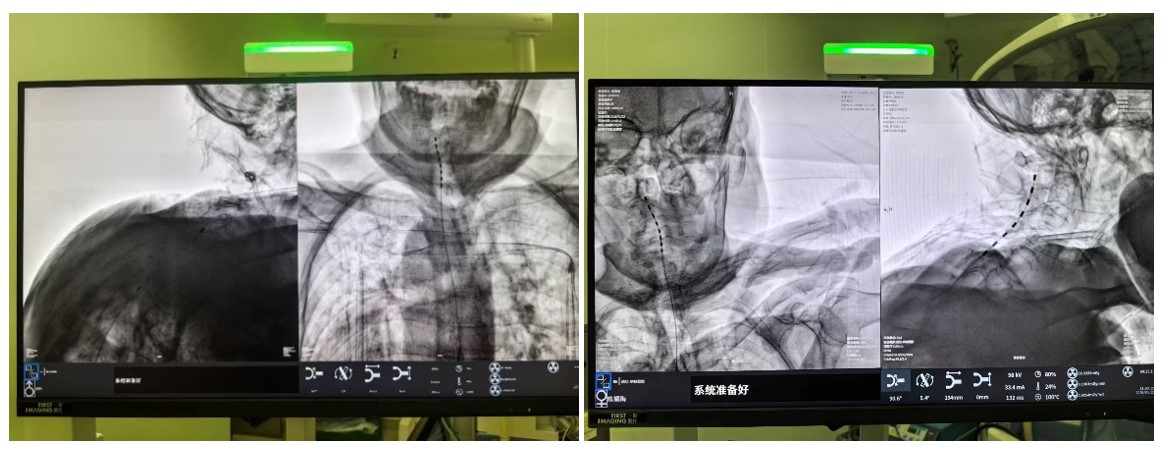

(C臂透视示术中电刺激已成功置入)

手术在局麻下进行,老人全程清醒。术中,当电极启动测试时,陈奶奶激动地反馈:“麻到了!颈根和肩胛都不痛了!”这种即时反馈确保了电极能够百分百覆盖痛区。术后一周,两位老人的疼痛视觉模拟评分(VAS,0分为无痛,10分为剧痛)从术前的8-9分骤降至2-3分,睡眠质量和情绪状态得到了质的改善。